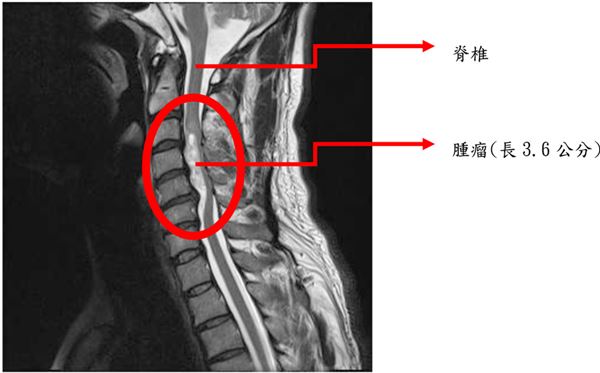

脊髓( spinal cord )是神經系統中重要的一部分。在顱頸的交會處,脊髓向上承接腦幹後,便被嚴密的保護在脊椎的神經腔中,由頸部一直延申到腰椎;右圖即是脊髓在脊椎內分佈情形。

脊椎內腫瘤

脊椎內原發性腫瘤依生長的部位不同,大致可分為三類:

第一類是生長於脊髓硬膜外( epidural )的腫瘤,最常見的是脊椎轉移癌,除了可能直接壓迫脊髓之外,也可能破壞脊椎體而造成病理性骨折。

第二類是生長在於硬膜內但是在脊髓軟膜外( extramedullary )的腫瘤,多半是良性瘤,最常見的是神經鞘瘤( schwannoma )及硬膜瘤( meningioma ),一般而言可經手術安全切除而不對神經功能造成任何影響。

第三類是生長於脊髓內( intramedullary )的腫瘤,最常見的是室管膜瘤( ependymoma )、星狀細胞瘤 (astrocytoma) ,也可經由手術徹底的切除。